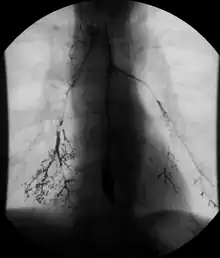

Barium follow-through showing the small bowel

• Barium follow-through examinations are used to study the small intestine.[2]

X-ray images are then taken in a supine position at intervals of 20–30 minutes. Real-time fluoroscopy is used to assess bowel motility. The radiologist may press or palpate the abdomen during images to separate intestinal loops. The total time necessary for the test depends on the speed of bowel motility or transit time and may vary between 1 and 3 hours.[17]

• Barium follow-through examinations are the most commonly used imaging technique in assessing patients with Crohn's disease, although CT and magnetic resonance imaging are widely accepted as being superior.[1] However Barium examinations remain superior in the depiction of mucosal abnormalities.[24] The features of Crohn's disease are well described by barium follow-through examinations, appearing as a typical "cobblestone pattern", but no information is obtained regarding extraluminal disease.[28] Radiographic imaging in Crohn's disease provides clinicians with objective evaluations of small bowel regions that are not accessible to standard endoscopic techniques.[29] Because of its length and complex loops, the small intestine is the most difficult part of the gastrointestinal tract to evaluate. Most endoscopic techniques are limited to the examination of proximal or distal segments, hence Barium follow-through remains in most centres the test of choice for the investigation of abdominal pain, diarrhoea and in particular diseases manifesting mucosal abnormalities such as coeliac and Crohn's disease.[26]